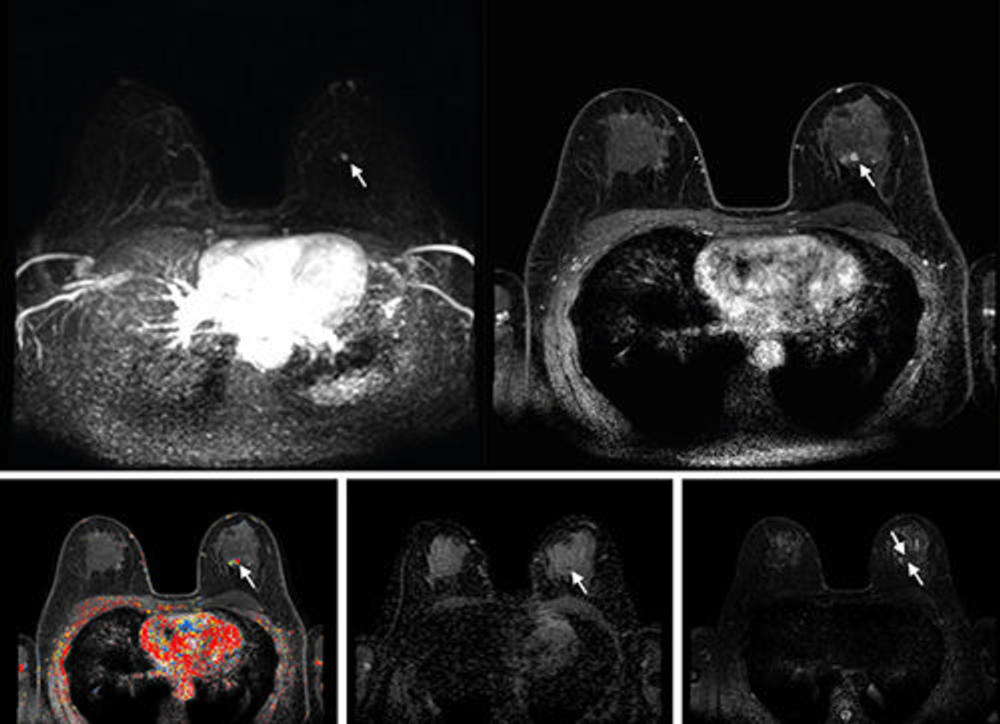

Figure 1. Axial images show the incremental steps 1–4. (A) Step 1: The first step consisted of the dual high-temporal low-spatial and low-temporal high-spatial dynamic T1 series, from before contrast material injection to 120 seconds after contrast injection only. (B) Step 2: The second step added diffusion-weighted images to the series available from step 1. (C) Step 3: The third step added T2-weighted images to the series available from steps 1 and 2. (D) Step 4: The fourth and final step added non–fat-saturated T1-weighted precontrast images, all remaining dynamic phases acquired after the first 120 seconds after contrast administration, and enhancement curve kinetics to the series available from steps 1, 2, and 3. This final step is the full multiparametric breast MRI protocol that was used in the Dense Tissue and Early Breast Neoplasm Screening (DENSE) trial. The curve kinetics overlay is a colormap showing the standard three types of delayed curve kinetics: type-I kinetics, persistent increase (blue); type-II kinetics, plateau (yellow); and type-III kinetics, washout (red).

Figure 4. Abbreviated axial MRI images show a 6-mm irregular mass with an irregular margin (arrows) in the right upper inner quadrant with early rapid enhancement. The lesion was assessed as Breast Imaging Reporting and Data System (or BI-RADS) category 4 (suspicious for cancer). The participant was recalled and underwent US-guided core-needle biopsy that showed invasive carcinoma of no special type. On the full-protocol sequences (not shown), the lesion was T2-weighted hypointense and showed diffusion restriction and washout kinetics in the delayed phase, characteristics that, although are all confirmative of the malignant nature of the lesion, offered no additional value for making the recall decision.

High-res (TIF) version

Figure 5. Abbreviated axial MRI images show a 7-mm irregular mass with irregular margin (arrows) in the right upper inner quadrant with early rapid enhancement (Breast Imaging Reporting and Data System category 4 [suspicious for cancer]). The participant was recalled and underwent an MRI-guided vacuum-assisted biopsy that showed sclerosing adenosis with microcalcifications and usual ductal hyperplasia and focal apocrine metaplasia. On the full-protocol images (not shown), the lesion was T2-weighted hypointense and showed diffusion restriction and washout kinetics in the delayed phase, characteristics that would not have reversed the decision to recall the participant.